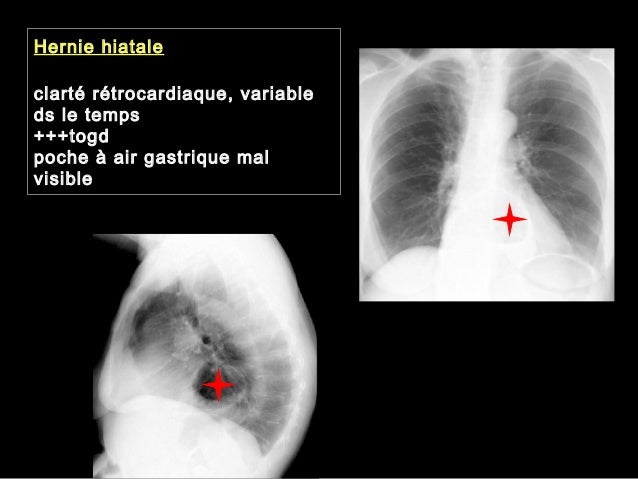

La hernie hiatale touche la partie supérieure de votre estomac Le hiatus est une fissure provoquée dans le diaphragme qui sépare la poitrine de l'abdomen 1 X Source de recherche Il existe deux types de hernies hiatales la hernie par roulement et la hernie par glissement. Hernie hiatale Thorax de face 1, Poumon droit 2, Trachée 3, Aorte 4, Poumon gauche Masse médiastinale rétrocardiaque avec niveau hydroaérique Les flèches rouges montrent le contour de la masse médiastinale, rétrocardiaque, ronde La flèche jaune pointe sur le niveau hydroaérique. Une hernie hiatale est le passage d’une partie de l’estomac dans le bas de poitrine a travers une zone de faiblesse dans le diaphragme La plupart des gens avec une hernie hiatale ne présentent pas de symptômes ou de problèmes Cependant, une hernie hiatale favorise le reflux acide dans l’œsophage, ce qui peut causer des.